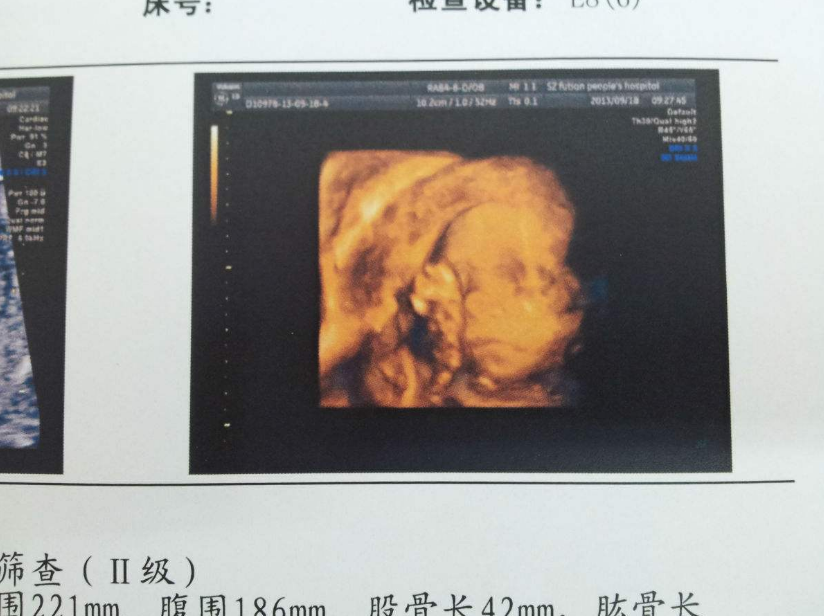

胎寶寶臍帶繞頸,說白了就是臍帶繞到脖子上了。在產(chǎn)科門診十分常見。